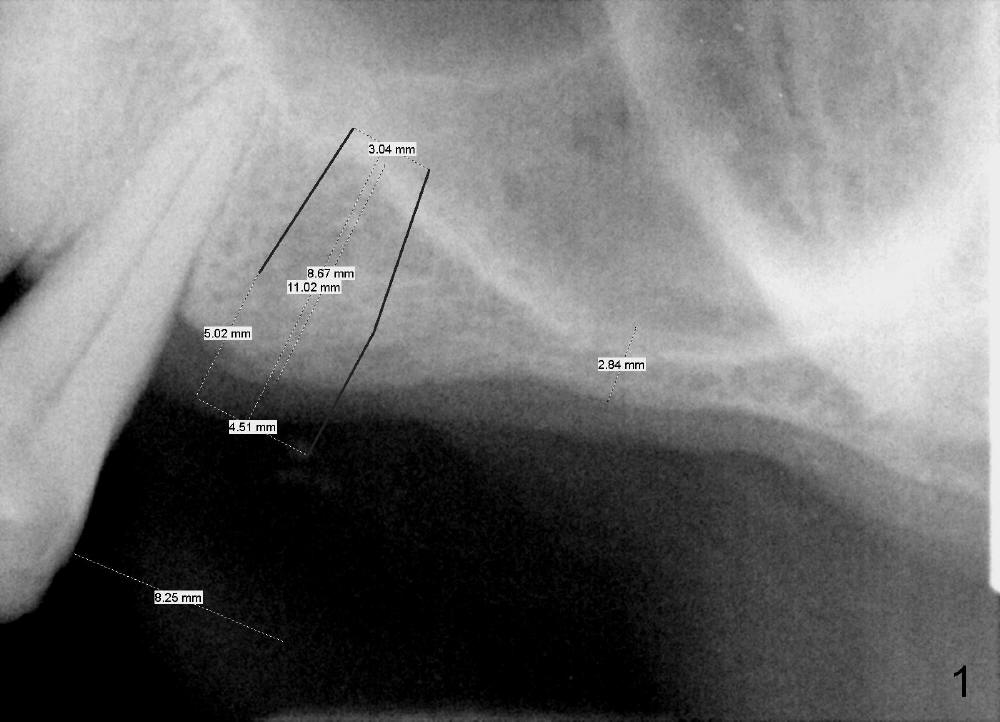

Davis has multiple missing teeth. We plan to place an implant at the site of #2, but he thinks that the tooth #31 is useless. Since there is an opposing tooth and implant placement at the site of #14 is challenging due to limited bone height (Fig.2: CT sagittal section), his first implant will be at the site of #13 (Fig.1-3). Two implant designs are gingiva- (Fig.1) and bone- (Fig.2,3 (coronal section) level.

CT analysis (Hounsfield units) shows D2/3 bone at the site of #13. Osteotomy is created by using drills. Fig.4 shows 3.5 mm drill at the depth of 8 mm. The trajectory needs to be adjusted. When 4 mm drill is done, the osteotomy is ovoid in shape. The implant should be 4 or 4.5 mm?